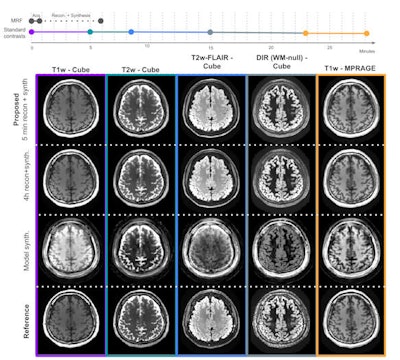

In the two test subjects, the synthesized T1-weighted magnetization-prepared rapid acquisition gradient-echo (MP-RAGE), T2-weighted, T2 fluid-attenuated inversion recovery (FLAIR), and double inversion recovery (DIR) images had highly similar slicewise structural similarity indexes compared with synthesized images produced from the reference reconstruction technique.

Timeline analyzing the MR fingerprinting acquisition and reconstruction protocol, which takes approximately six minutes (of which the patient is required to be still for one minute), compared to the time required to acquire conventional contrasts (approximately 28 minutes). The above image comprises five synthesized contrasts in the test subject using the proposed method (row 1), a much slower reconstruction (row 2), a simple model-based synthesis (row 3), and the reference scans (row 4). Images and caption courtesy of Sophie Schauman and ISMRM."Future directions of the project include continued clinical data collection, with the aim to include patients in the training data set using semisupervised methods and improved robustness of the pipeline regarding patient positioning in the field of view," Schauman said. "We also aim to further optimize the time/quality trade-off by acquiring faster B0 and B1 maps for calibration of quantitative imaging."